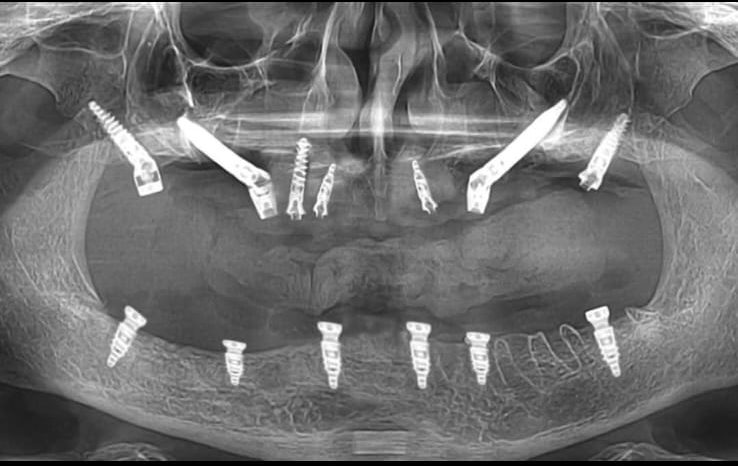

Full Mouth Implant Case

Full Mouth Implants with all Ceramic Crowns